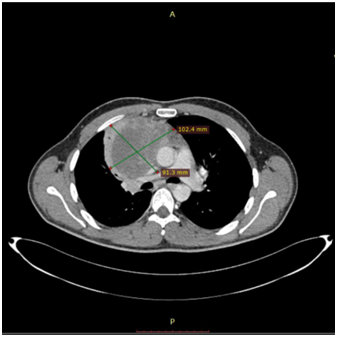

The 1st case we report is of a 22-year-old Caucasian male, who was admitted to our hospital with a 3-days history of progressive dyspnea on exertion, neck swelling, fatigue, persistent chest pain, pyrexia, and a cough that was occasionally productive of blood. The physical examination revealed a heart rate of 115 beats per minute (Sinus Rhythm), a respiratory rate of 25 breaths per minute and superficial vascular distention over the neck. Laboratory studies revealed elevated serum α-fetoprotein (AFP) (5380 IU/ml) and D-dimer (481ng/ml). A chest X-ray in the poster - anterior view, upon admission, depicted a suggestive right upper mediastinal mass (Bild 1). Radiography was followed by contrast-enhanced CT scan that revealed a large, homogeneous mediastinal mass crossing into the anterior mediastinum and compressing – encasing the superior vena cava. It also showed signs of thrombosis of the left brachiocephalic vein, and multiple filling defects at the left pulmonary artery indicating embolism. Subcarinal lymphadenopathy, as well as enlarged lymph nodes of the right hilum was present (Bild’s 2-5). On median sternotomy, a large non resectable tumor was observed involving the in nominate vein and the superior vena cava (Bild 6). Great care was taken to remove as much tumor mass as possible. To decompress the superior vena cava, we had to perform an extensive resection and reconstruction of the cephalad part of the superior vena cava using homolog pericardium.A histopathological examination of a section of the mass revealed a mixed NSGCT (embryonal yolk sac/endodermal sinus tumour), containing also elements of embryonal carcinoma (Figure 1-6).The patient was placed on cisplatin-based chemotherapy (BEP regimen: cisplatin 50mg/m2 on days 1-2, etoposide 165mg/m2 on days 1-3, bleomycin 30U on days 1, 8, and 15, every 3 weeks). Tumor markers were elevated for a-FP (214ng/mL) and normal for β-HCG. The patient completed 4 cycles of chemotherapy and the subsequent chest CT (Bild 7) revealed a partial remission of the mass (decrease>50% of the size). The a-FP was normal as well as the β-HCG. The remaining mass was inoperable so the patient was started on salvage chemotherapy with the TIP (paclitaxel, ifosfamide, ciplatin) regimen for 4 cycles. The post-chemo chest CT showed stable disease and the patient was referred to radiation oncologists for radiotherapy of the remaining tumor. Three months later af P was found elevated and the CTs revealed multiple brain metastases. Whole brain radiation was performed and the patient was placed on gemcitabine (d1 and d8 every 21 days). Two months later the neurologic status deteriorated with new brain metastases and the patient passed away (19 months after the diagnosis).

Bild 7 CT – axial plan of the Yolk sac tumor after chemotherapy.